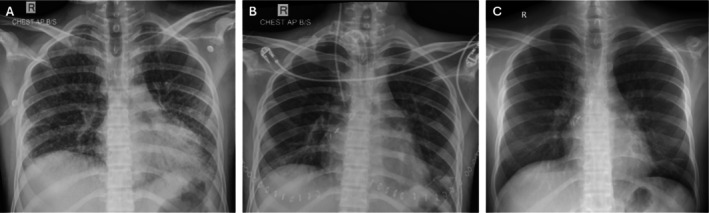

Paraquat, a commonly available herbicide, when consumed in high doses, affects organs with high blood flow (lungs, heart, kidney and liver), leading to pulmonary fibrosis, respiratory failure and death. Few reports of rescue lung transplantation exist. Complete depletion of paraquat from the body is necessary prior to transplant; however, timing for and concerns after lung transplantation remain unknown. We report 2 patients (median age 19 years) with severe respiratory failure requiring extracorporeal membrane oxygenation support, acute kidney injury requiring haemodialysis and acute liver injury in the pre-transplant period. Volume of paraquat consumption was more than 30 mL and PF ratio less than 100 before transplant. Once their urine paraquat level was negative (median time 32 days), both underwent bilateral lung transplantation after receiving an induction agent with basiliximab and were continued on triple immunosuppressant following the transplant. With reported mortality rates reaching up to 90%, lung transplantation remains a reasonable option for patients with paraquat poisoning not responding to conventional treatment options. Once paraquat levels are negative and after optimising renal and liver function, these patients could be considered for bilateral lung transplantation and have successful outcomes as reported here.